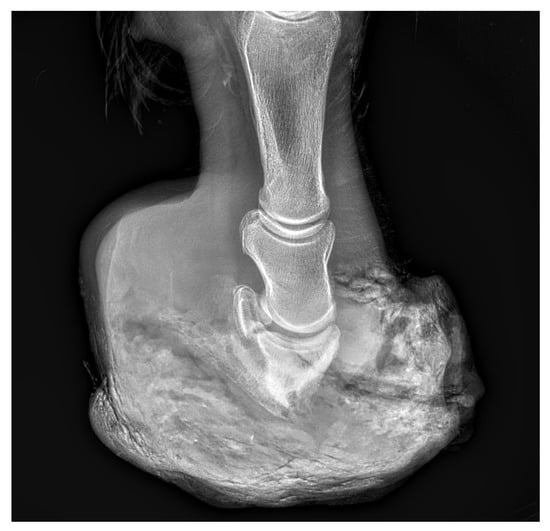

Case Presentation